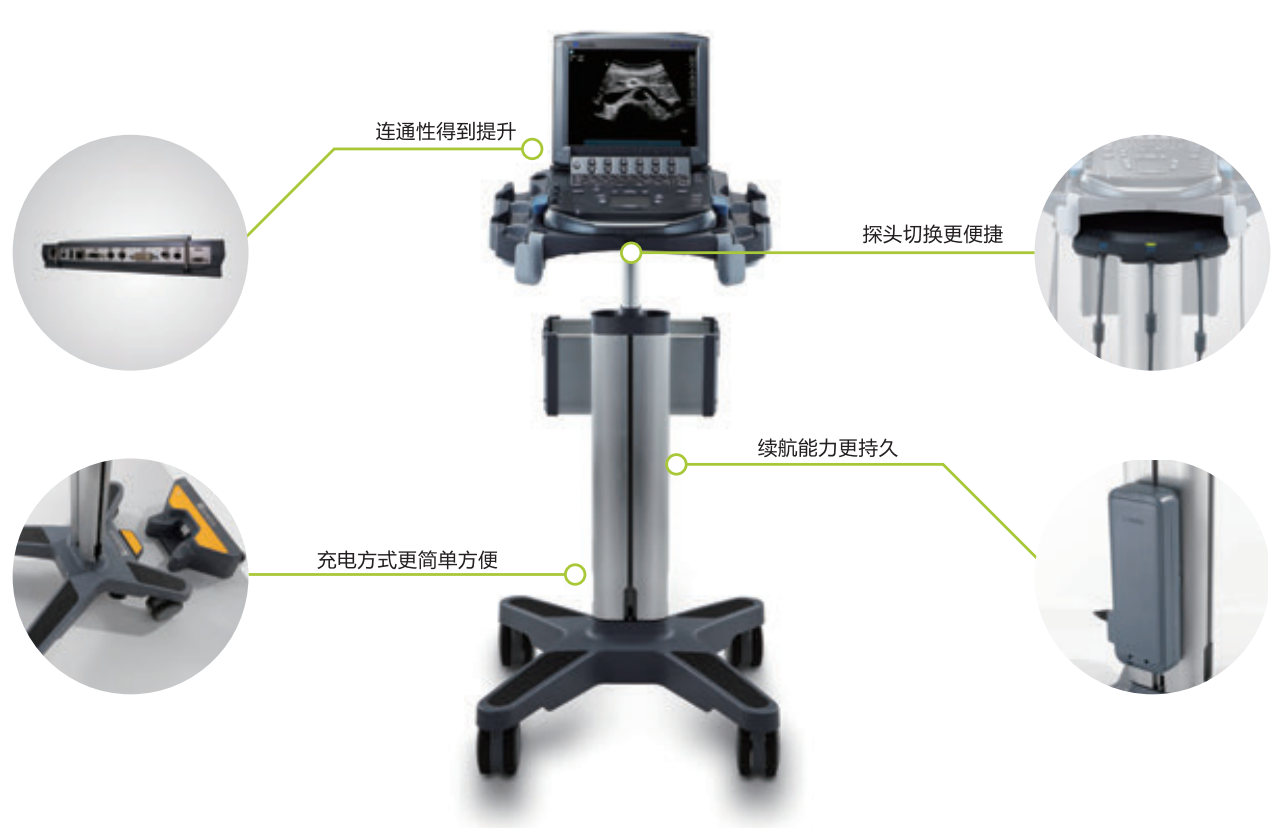

M-Turbo 便攜式彩色超聲診斷系統(tǒng),源自嚴苛的設計標 準,以優(yōu)異的圖像質量和產(chǎn)品性能,引領POC可視化超 聲應用領域發(fā)展,讓醫(yī)生更從容地將更細致入微的醫(yī)療關護帶給患者。

耐用 |

鎂合金外殼設計 無針式探頭接口 耐約1米跌落試驗 5年原廠質保 |

便攜 |

體積小巧,主機重3.4kg,電池續(xù)航達4小時 12秒快速啟動 |

可靠 |

專利ASIC芯片技術,專業(yè)級V×Work操作系統(tǒng) 更為穩(wěn)定,更為可靠 |

易用 |

10.4"屏幕尺寸,SonoADAPTTM 技 術 AutoGainM 技術 調節(jié)更為簡便 |